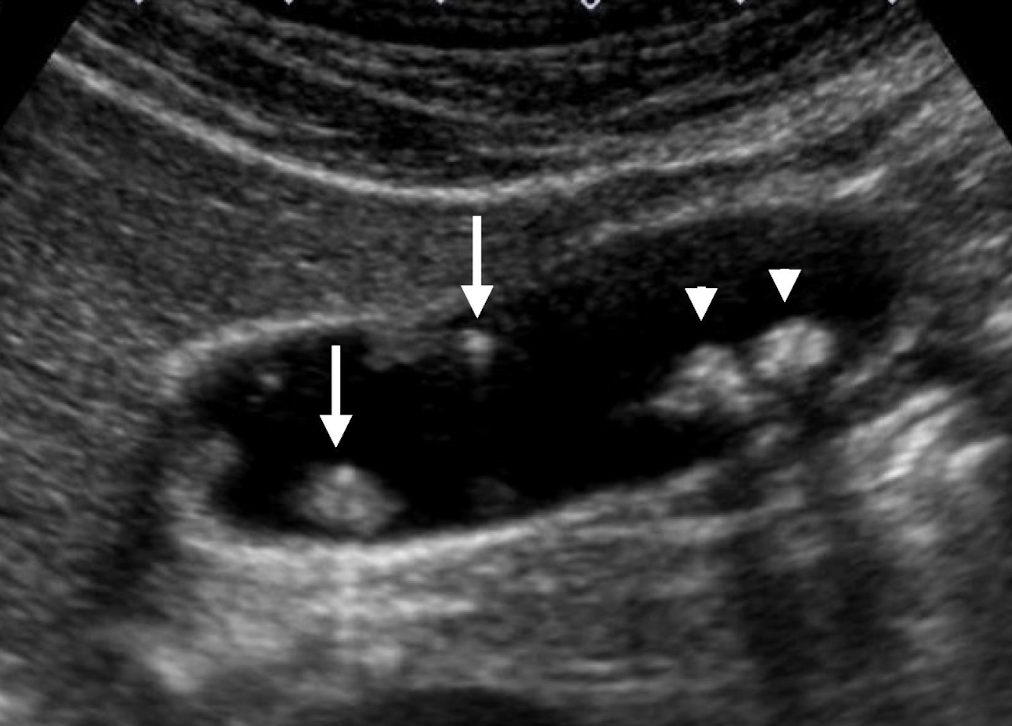

SONO: cholelithiasis

twinkle artifact

posterior shadow (due to refraction, impedance, intensity of the sound beam, and stone(s) size)

??

cholelithiasis

calcified stones with posterior shadowing